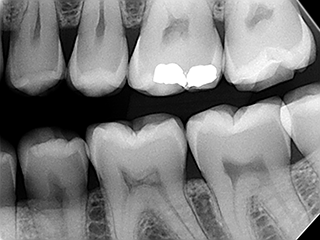

Wisdom Tooth RemovalDigital X-Ray

Allows instant x-ray which the patient can immediately see on the screen.

Gives out less radiation when compared to conventional x-ray.

Less time-consuming.